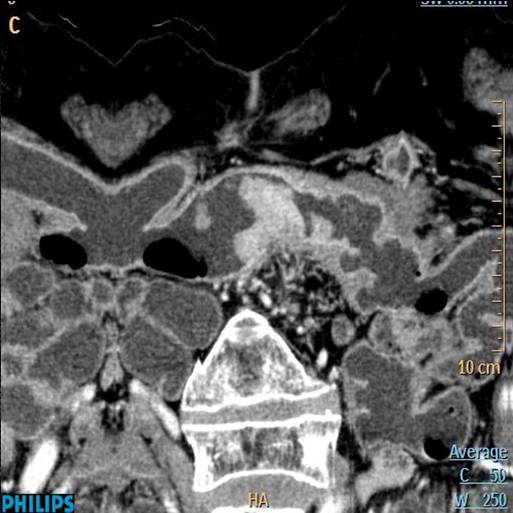

结肠癌